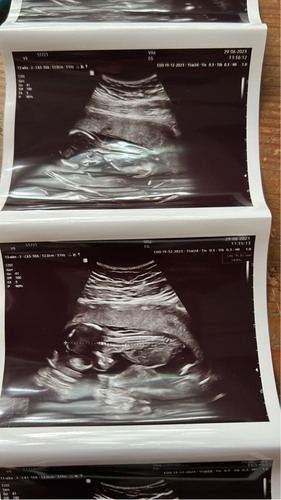

Hier was ik 13+3 komende woensdag pretecho waarbij we het weten dan 17 weken 🥰